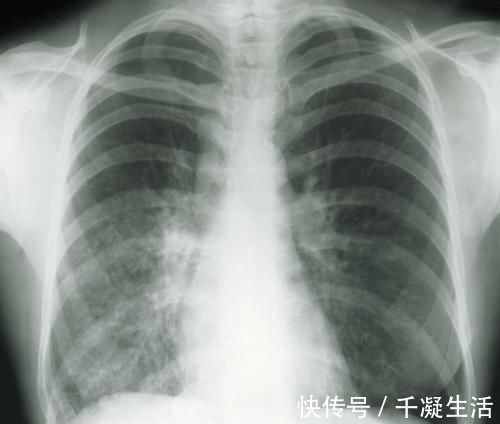

近期,陈女士来到医院复查,薄层CT扫描结果显示,陈女士左肺为磨玻璃结节,且有增大现象,考虑恶性可能度高。

术后病理结果显示,陈女士体内的肺结节,最大的仅有0.9cm,但已发展为早期浸润肺癌,一个为原位腺癌,0.4cm,其他的均为炎症性结节。

肺磨玻璃结节一般是在做胸部CT时发现,表现为密度轻度增高的云雾状淡薄影或圆形结节,样子像磨砂玻璃,所以叫磨玻璃影。可以是弥漫性散在生长,也可以聚集在局部,看起来就像一个小磨玻璃结节。